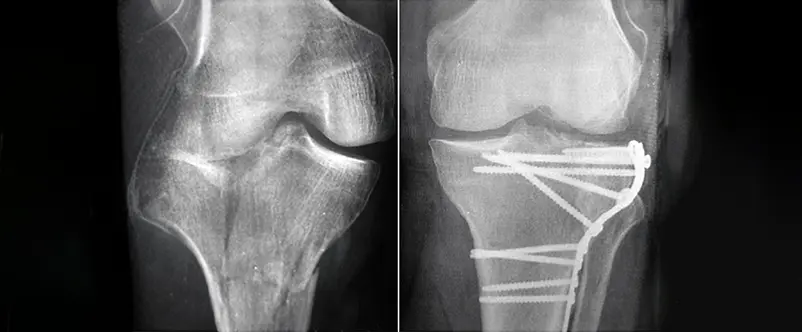

Frattura del Piatto Tibialestaff@2026-03-10T09:56:47+00:00 Frattura del Piatto Tibiale Chirurgia Traumatologica